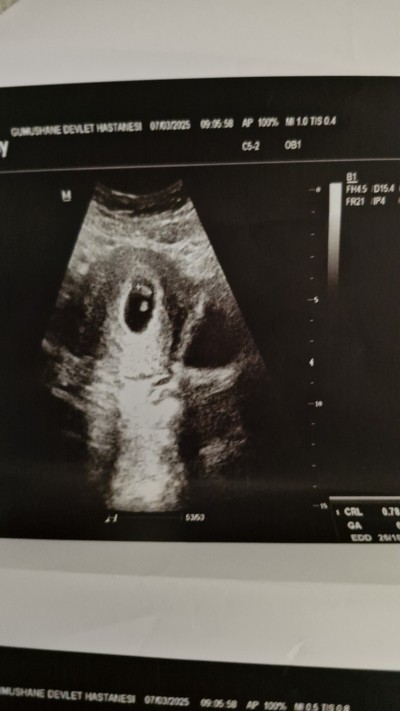

7. Haftadayım kontrolde doktor ikizden şüphelendi ama kesin değil dedi bu haftada belli olmaz mı aranızda yaşayan varmı

Gebelik haftası 7

Devlet hastanelerin cihazı pek iyi olmadığı için emin olamiyorlar benimde iki kese vardı devlet hastanesinde görülmedi özele gittim çift kese vardı ama birinde bebek gelismedi şuan tek bebek olarak devam ediyoruz bir dahaki kontrolde daha net olur sizinkide

Teşekkür ederim benimde tek kesede ikiz gibi gözüküyor ama kesin değil dedi 2 hafta beklicem ama sabırsızım baya.